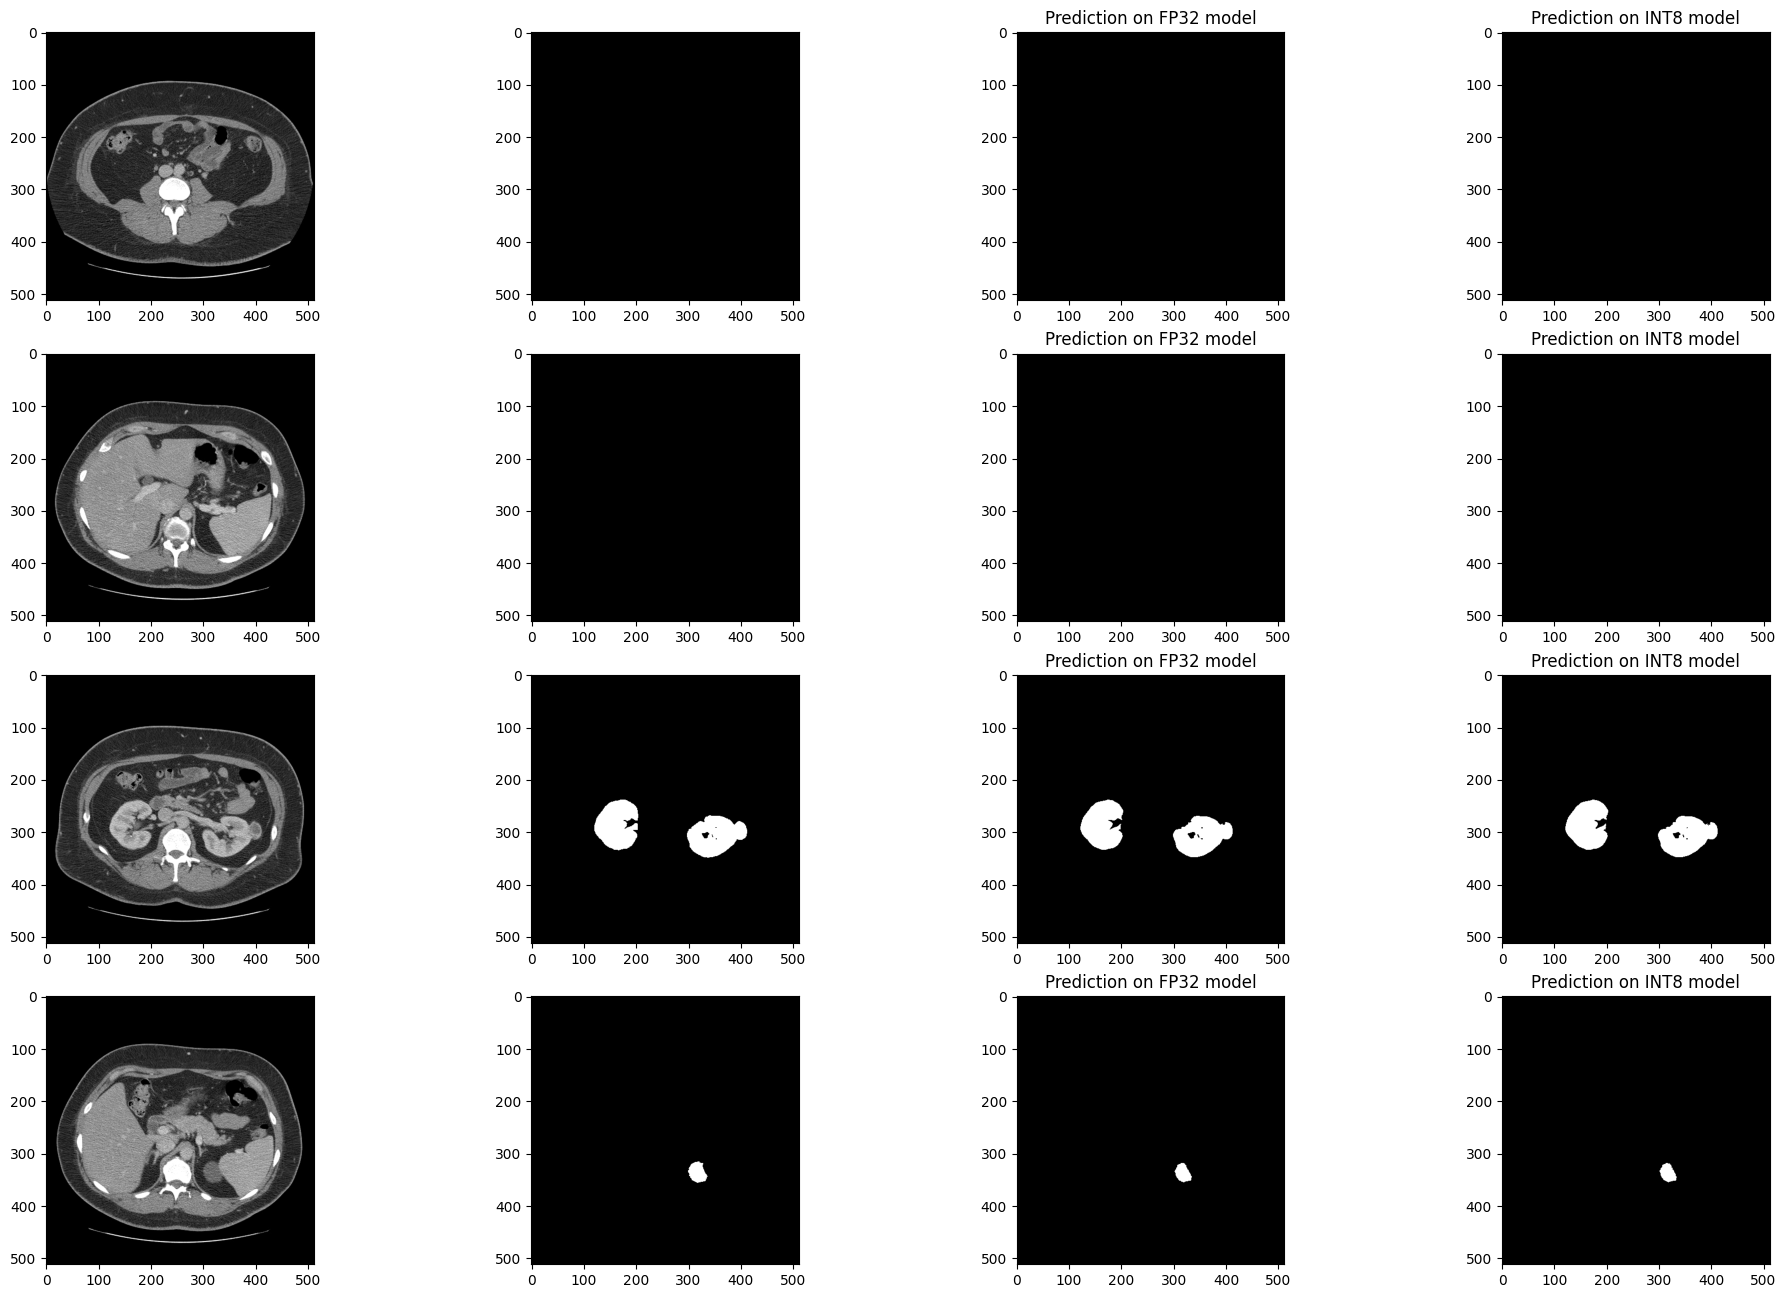

推論結果を視覚的に比較#

検証セットの 4 つのスライスでモデルの結果を視覚化します。FP32 IR モデルの結果を、量子化された INT8 モデルおよびリファレンス・セグメント化アノテーションの結果と比較します。

医療画像データセットは不均衡になる傾向があります。CT スキャンのスライスのほとんどには腎臓データが含まれていません。セグメント化モデルは、腎臓が存在する場所で腎臓を見つけるのに優れている (医学用語: 感度が良い) 必要がありますが、存在しない偽の腎臓は見つけない (特異度が良い) 必要があります。次のセルには 4 つのスライスがあります。2 つのスライスには腎臓のデータがなく、2 つのスライスには腎臓のデータが含まれています。この例では、スライス内の少なくとも 50 ピクセルに腎臓としてアノテーションが付けられている場合、スライスに腎臓データがあります。

このセルを再度実行すると、別のサブセットの結果が表示されます。ランダムシードは、このセルの特定の実行を再現できるように表示されます。

注: 画像はオプションで拡大およびサイズ変更を行った後に表示されます。Kits19 データセットでは、1 つを除くすべてのケースの入力形状が

(512, 512)です。